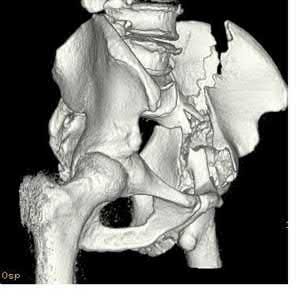

Figures A-C are a 32-year-old female who presents to the trauma bay after falling off a roof. Paramedics state that she was initially complaining of back pain, but she now appears irritable and lethargic. She has received 2 liters of crystalloid since arriving in the trauma bay. Her blood pressure is now 76/42. A Foley catheter is placed, and her urine output is 12 ml/hour. What additional finding would suggest hemorrhagic shock over neurogenic shock?

This patient sustained a multi-traumatic injury and is suffering from hemorrhagic shock. The presence of tachycardia would favor the diagnosis of hemorrhagic shock over neurogenic shock.

In initial hypovolemic shock (stage I,

Figures A-C: The initial radiographs reveal the posterior subluxation of the talus with associated posterior subluxation of the fibula without significant coronal plane deformity. This deformity should raise the suspicion of a Bosworth fracture-dislocation, especially if closed reduction is not successful. Figures D and E: Axial CT images demonstrating Bosworth fracture-dislocation of the fibula entrapped behind the tibia. Also, note the fracture extension to the posteromedial rim in this posterior pilon variant.

Figure F: Positioning of the plate suggests a posterolateral approach to address both the fibula and posterior malleolus fractures.